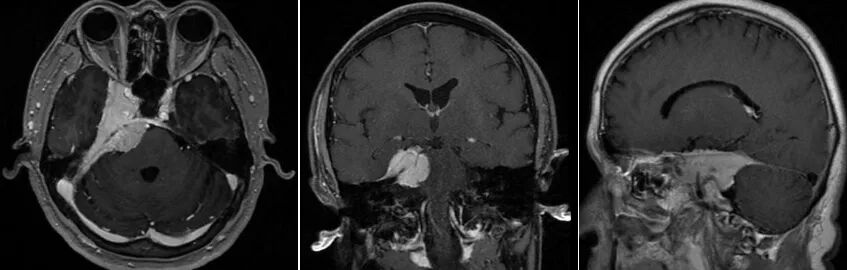

患者术前MRI

近日,广东药科大学附属第一医院神经外科成功为一名复杂脑肿瘤患者实施了脑肿瘤切除术。前段时间,原本身体健康的肖先生,莫名其妙出现右侧颜面部疼痛,洗漱、进食、受凉后疼痛加重。难以忍受的肖先生到医院检查才发现,原来是颅内生长了一个鸡蛋大的肿瘤,大小约48mm×60mm×23mm,而且肿瘤位于脑子深部,手术难度高、风险大,术后并发症也极其复杂。